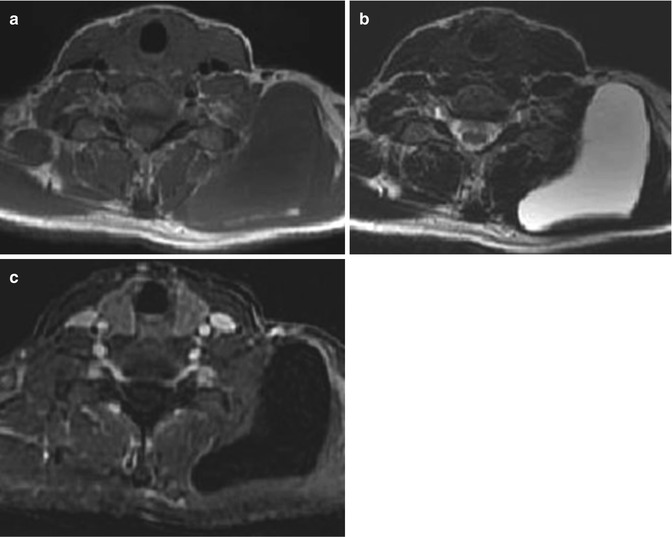

Klippel-Trenaunay syndrome in a 30-year-old boy. (a) Coronal T2-weighted MR image with fat suppression. (b, c) Axial T2-weighted MR images with fat suppression of the pelvis and thigh. (a–c) There is hemihypertrophy of left lower extremity with extensive subcutaneous (star) and intramuscular venous malformations. Note the characteristic abnormal sapheneous vein (arrowhead in c)